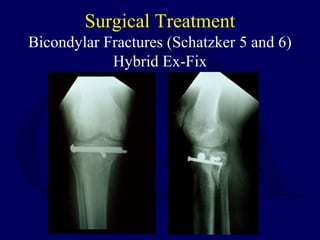

Bicondylar Fractures (Schatzker 5 and 6)

Hybrid Ex-Fix

Hybrid External Fixation

Results

• Duration external fixation 12-16 weeks